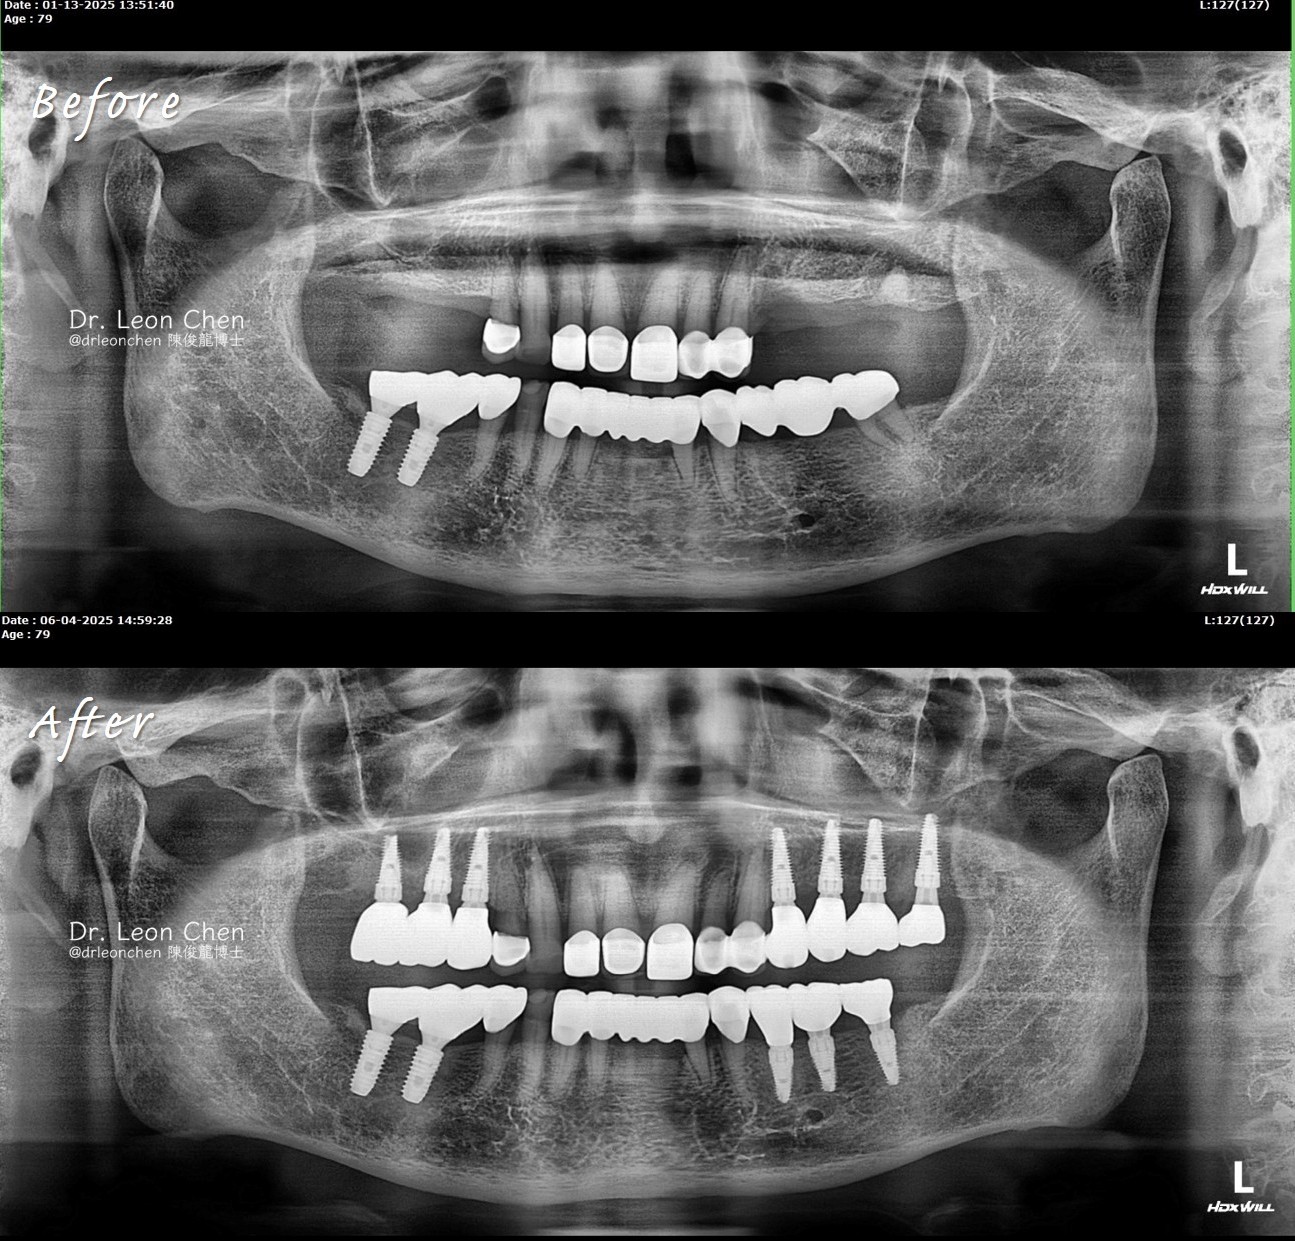

精奈創一鑽植牙系統團隊|10顆植牙,不用再等到90歲

79歲的初診患者,之前右下兩顆植牙歷時2年多才完成,讓他嚇到不敢再植牙,他想:「植2顆要花2年,那植十顆可能要植到90歲了」。

陳博士用精奈創一鑽植牙系統,僅花4個月又20天,就讓他完成了10顆植牙的整個療程、結果穩定,徹底改變了他對植牙的印象。